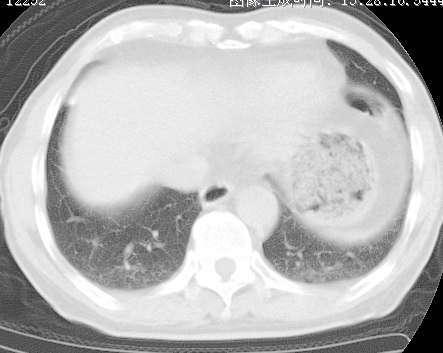

标题: CT24032:男65岁,咳嗽,吸烟20余年,无发热,咳痰 [打印本页]

标题: CT24032:男65岁,咳嗽,吸烟20余年,无发热,咳痰

考虑右肺中叶不张,请大家发表意见

右肺中叶支气管闭塞,中叶肺不张,右侧肺门见肿块影。中心型肺癌的可能大。建议支气管镜检查。

右肺门旁类圆形肿块影,右肺中叶不张,建议纤支镜检查。

1右肺门旁类圆形肿块影,右肺中叶不张,建议纤支镜检查

2右侧胸膜增厚,右侧叶间胸膜区钙化

3右肺下叶小囊状透亮影考虑肺气肿